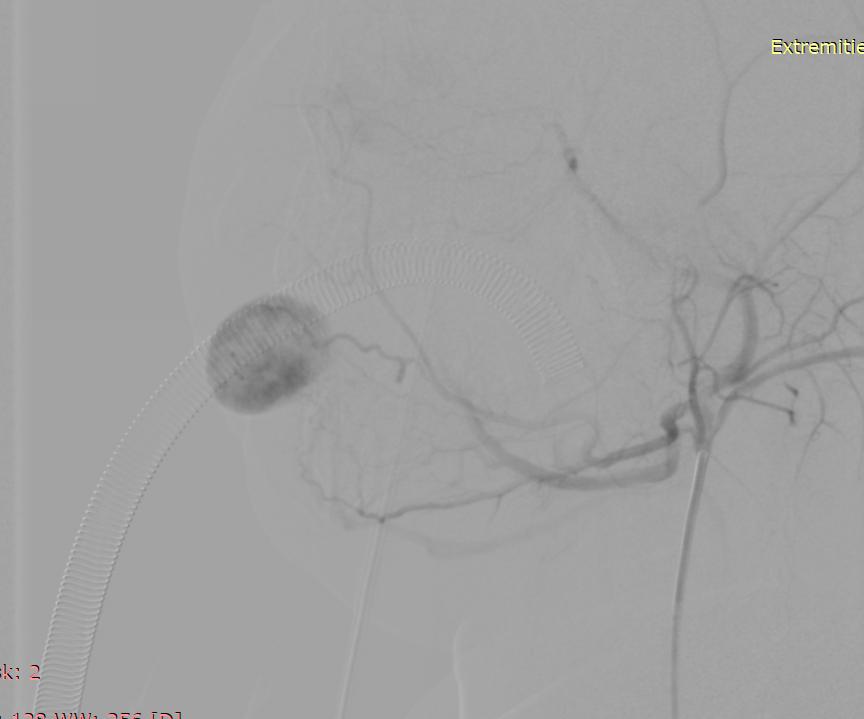

术中情况

栓塞后